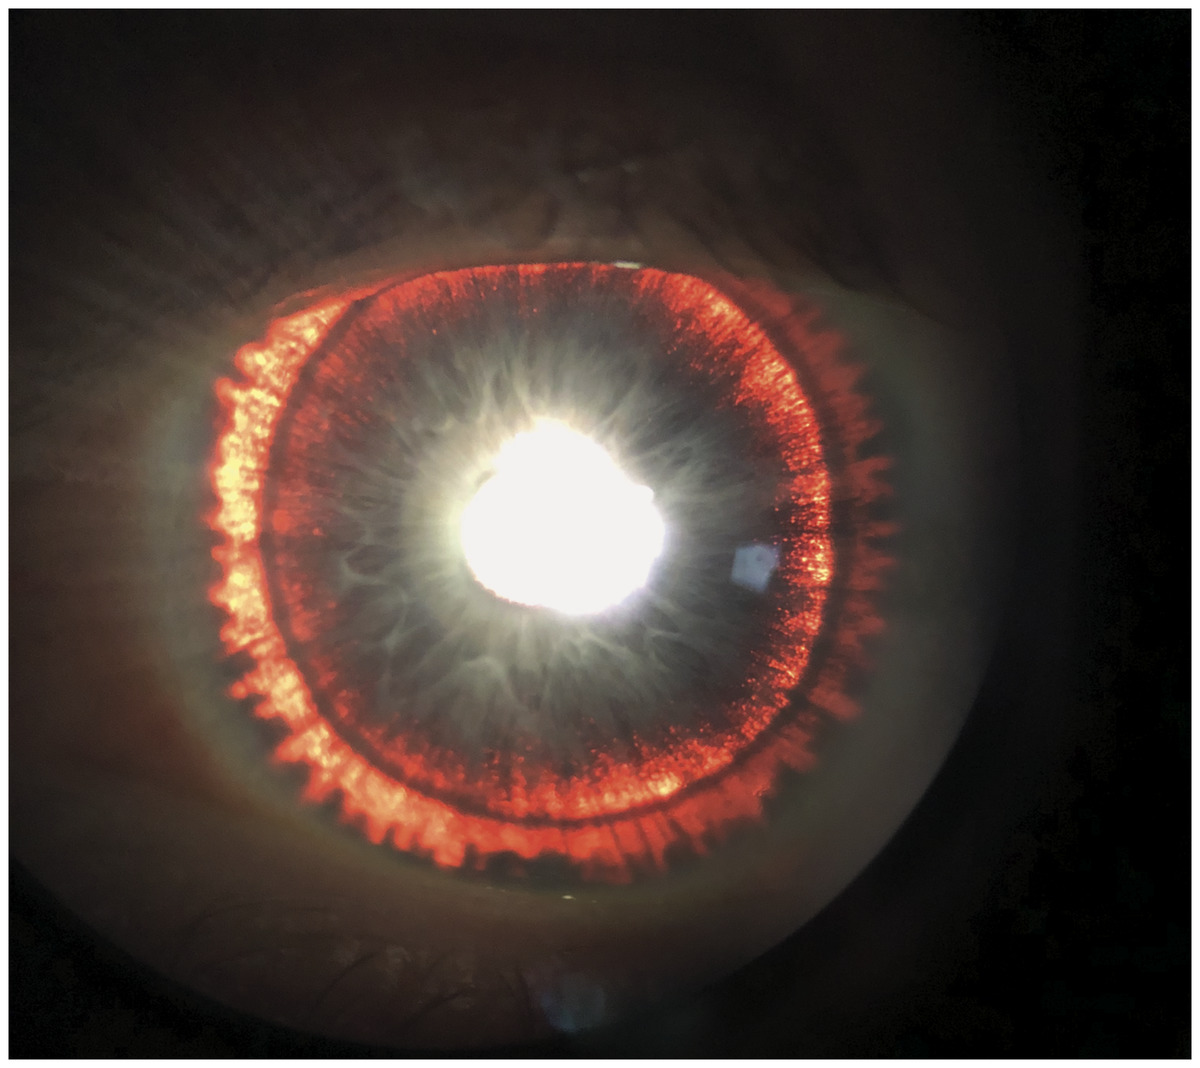

홍채를 관찰하면 방사상 모양으로 투시결손이 나타납니다.

즉, 홍채에서 색소가 탈락한 부분에는 빛의 투과가 많아 지므로,

그 부분이 투명하게 관찰 되게됩니다.

전방각경 검사를 하면 섬유주 전반에 걸쳐

짙고 균일한 어두운 갈색의 색소띠가 관찰됩니다.